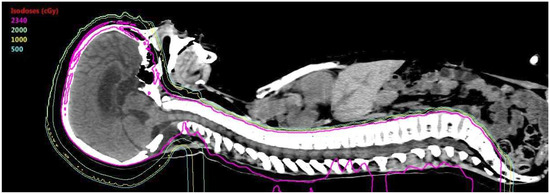

- Brower, J.V.; Gans, S.; Hartsell, W.F.; Goldman, S.; Fangusaro, J.R.; Patel, N.; Lulla, R.R.; Smiley, N.P.; Chang, J.H.; Gondi, V. Proton therapy and helical tomotherapy result in reduced dose deposition to the pancreas in the setting of cranio-spinal irradiation for medulloblastoma: Implications for reduced risk of diabetes mellitus in long-term survivors. Acta Oncol. 2015, 54, 563–566. [Google Scholar] [CrossRef] [PubMed]